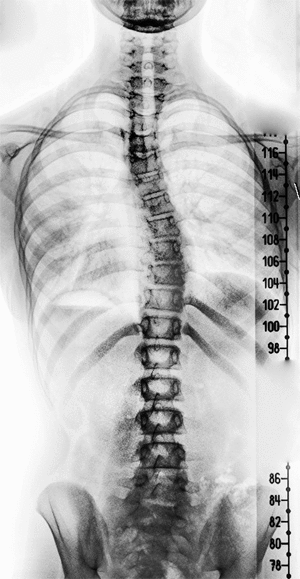

TDN > Actualité Le corps humain aux rayons X … en GIFs animés ! Publié par Elsa Fanjul le 11 Jan 2014 à 10:08 Suivez nous sur Google News Partagez cet article En bonus, découvrez le Giphoscope, ou comment faire des GIFs dans la vraie vie ! Veuillez laisser ce champ videRejoignez nos 875 726 abonnés en recevant notre newsletter gratuite N'oubliez pas de cliquer sur l'email de validation pour confirmer votre adresse email. Si vous ne l'avez pas recu vérifiez dans vos spams. Dernière étape pour confirmer votre inscription : il faut cliquer l'email de confirmation. Vérifiez dans vos spams si vous ne l'avez pas reçu ! A bientôt ! Page précédente Laissez un commentaire Votre adresse e-mail ne sera pas publiée. Les champs obligatoires sont indiqués avec * Votre commentaire * Votre pseudo * Votre adresse e-mail * Cliquez ici pour commenter